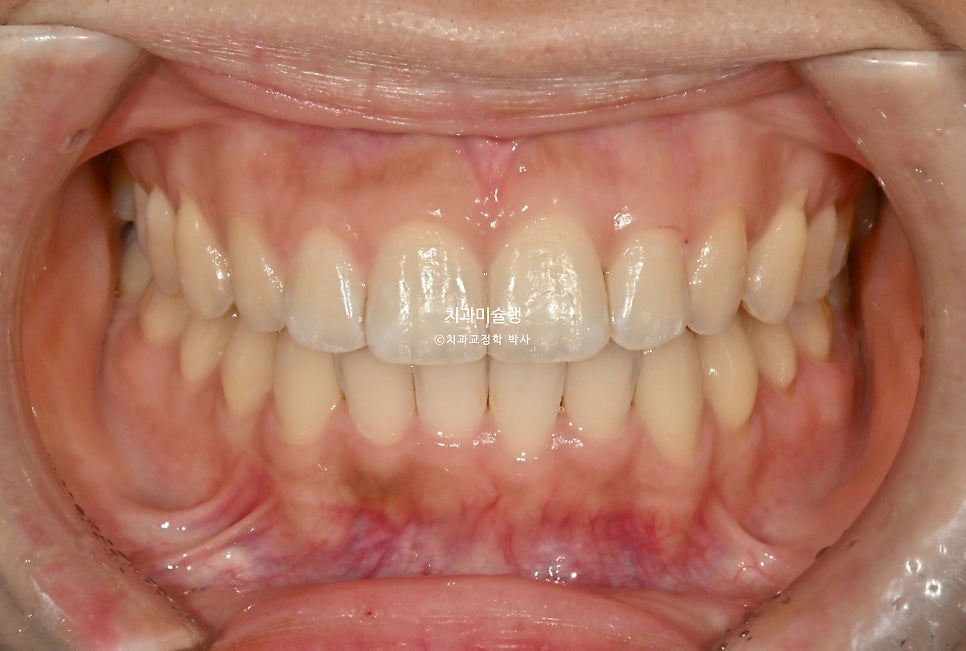

2026년 2월 – 치료 완료

추가장치를 약 2달간 낀 후 206년 2월, 치료를 마무리 했습니다.

총 치료기간은 7개월, 재제작은 1회 했습니다.

이제 전후 비교 보겠습니다.